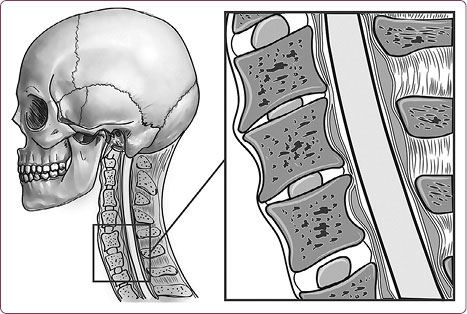

Рис. 5. Межпозвоночные диски шейного отдела позвоночника

Шейный отдел позвоночника, состоящий из семи позвонков, должен иметь достаточную длину и определенную статику (рис. 7).